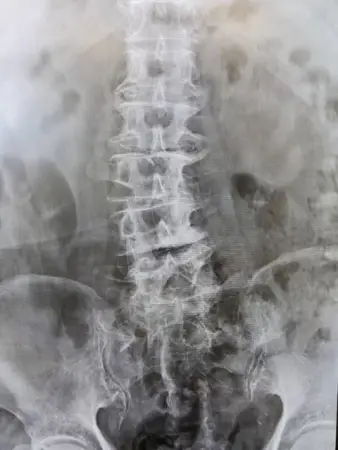

下記の写真は、本物の背骨(同一人物)です。関節面を丸で囲っていますが、ウサギの耳みたいになっています。頚椎と胸椎と腰椎とでは、それぞれのウサギの耳の角度が全く異なります。